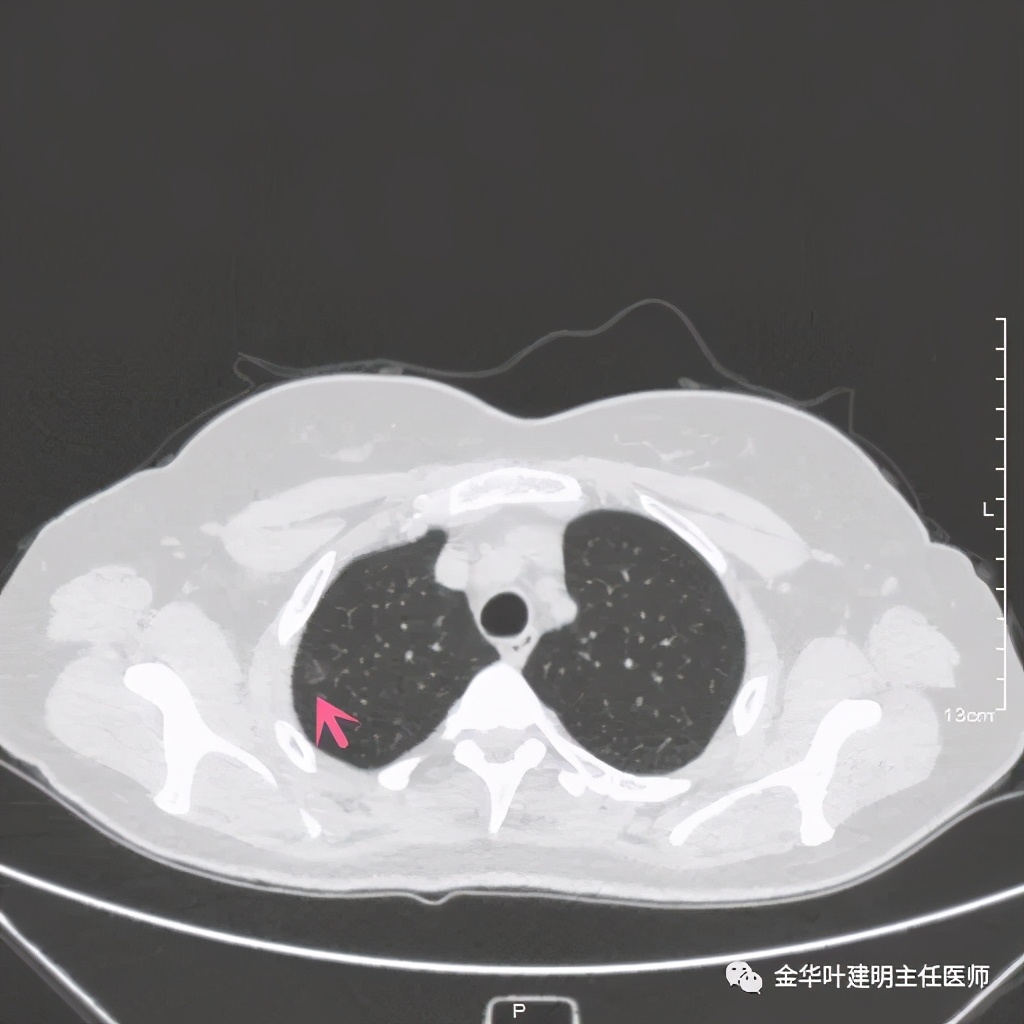

上图示病灶2,密度低,但轮廓相对也是清楚的,考虑腺瘤样不典型增生可能性大

上图显示的是后段与尖段支气管开口处,蓝色箭头所指是尖段支气管开口,粉红色箭头示后段支气管,绿色箭头示后段外亚段支气管的走行。